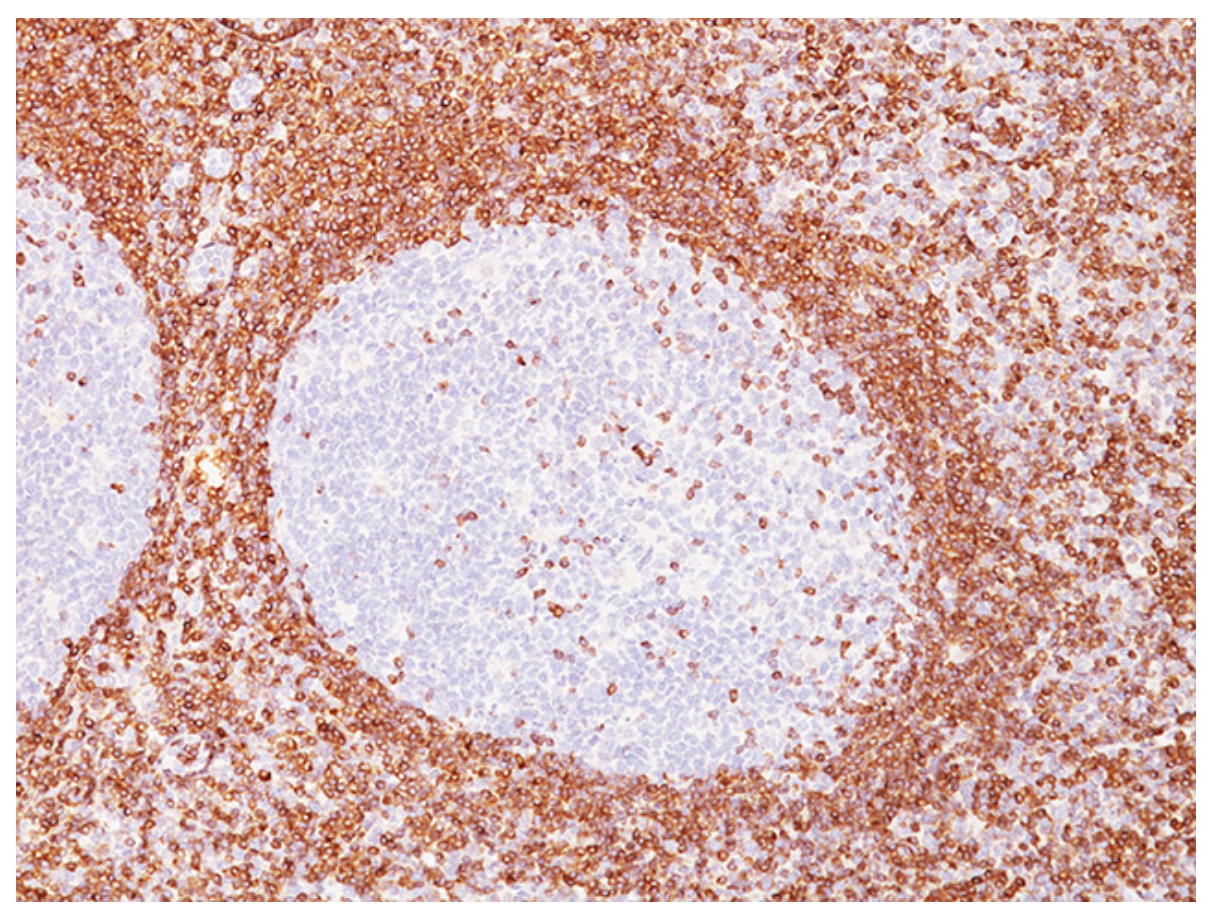

A imagem abaixo mostra um corte histológico de biópsia de linfonodo cervical REACIONAL com marcação imunohistoquímica para BCL6. Qual outro marcador apresentaria o MESMO padrão?

Nos folículos linfoides SECUNDÁRIOS, as células B naïve entram em contato com o antígeno e sofrem o processo de HIPERMUTAÇÃO SOMÁTICA e TROCA DE CLASSE da imunoglobulina.

Para permitir a ocorrência do processo de SELEÇÃO NEGATIVA das células B cuja afinidade contra o antígeno foi PREJUDICADA após sofrerem hipermutação somática, ocorre DIMINUIÇÃO fisiológica da transcrição de BCL2 (molécula anti-apoptótica) a partir do momento que as células entram no centro germinativo.

Em paralelo, ocorre aumento de expressão das moléculas BCL6 e CD10, típicas dessa fase de maturação.

Portanto, nos folículos linfoides secundários REACIONAIS, a marcação por imunohistoquímica mostra POSITIVIDADE para BCL6 e CD10 e NEGATIVIDADE para BCL2.

No folículo linfoide secundário NORMAL, qual marcador apresenta o seguinte padrão na imunohistoquímica (mostrado abaixo)?

B) BCL2

O centro germinativo é a estrutura CENTRAL dos folículos linfoides SECUNDÁRIOS, onde as células B naïve entram em contato pela primeira vez com seus respectivos antígenos, sofrem o processo de expansão clonal e HIPERMUTAÇÃO SOMÁTICA (na zona escura) e TROCA DE CLASSE da cadeia pesada da imunoglobulina (na zona clara).

Após o processo de HIPERMUTAÇÃO SOMÁTICA, a afinidade da célula B por seu antígeno pode melhorar ou piorar.

Caso a hipermutação somática provoque efeito DESFAVORÁVEL na afinidade pelo antígeno, ocorrerá SELEÇÃO NEGATIVA e apoptose da célula.

Para isso ocorrer, é essencial que as vias de apoptose estejam preservadas, o que inclui a inativação da molécula anti-apoptótica BCL2. Qualquer prejuízo nesse processo pode levar à linfomagênese, como é observado no linfoma folicular, que expressa BLC2 inapropriadamente no centro germinativo.

Sendo assim, a pesquisa de BCL2 por imunohistoquímica no linfonodo NORMAL ou REACIONAL mostra padrão típico de coloração POSITIVA nas células da zona do manto (localizada ao redor do centro germinativo e constituídas por células B naïve) e NEGATIVA no interior do centro germinativo.

As poucas células localizadas no interior do centro germinativo que apresentam marcação POSITIVA para BCL2 são na realidade linfócitos T.

Da mesma maneira, as células localizadas no paracórtex e na região interfolicular POSITIVAS para BCL2 também são linfócitos T.

A marcação para CD10 e BCL6 teria padrão inverso, uma vez que ambas são expressas DENTRO do centro germinativo.